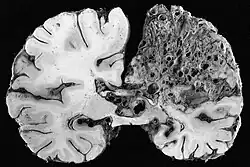

| Large arteriovenous malformation of the parietal lobe | |